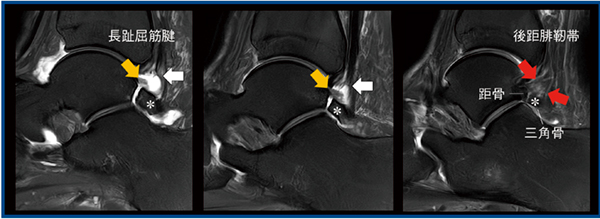

足関節では頻度の高い,三角骨という種子骨を有する症例を提示する。本症例は踵の奥が痛く底屈できないという,いわゆる後方インピンジメントを示唆する所見で来院し,MRIのT2強調画像にて長趾屈筋腱の断裂を認めた。腓骨遠位端から距骨背側および三角骨に向かう後距腓靭帯は,通常,距骨後方突起に付着するが,三角骨がある場合は三角骨と距骨の両者にさまざまな程度に付着する。本症例では,後距腓靭帯の三角骨に付着する領域が完全に断裂し,弛緩していた。脂肪抑制プロトン密度強調画像の矢状断像(図4)では,PIQEを適用することで長趾屈筋腱の断裂によるフレアリング(←)が明瞭に描出され,また,後距腓靭帯(→)の三角骨(*)と距骨への付着の割合を確認することができる。本症例では後距腓靭帯の大部分が三角骨に付着しており,通常の三角骨摘除や長趾屈筋腱再建術では術野に十分に含まれないため(図4→),後距腓靭帯の再建を外科医に提案する必要がある。

図4 PIQEによる長趾屈筋腱の断裂および三角骨への後距腓靭帯の付着部の描出